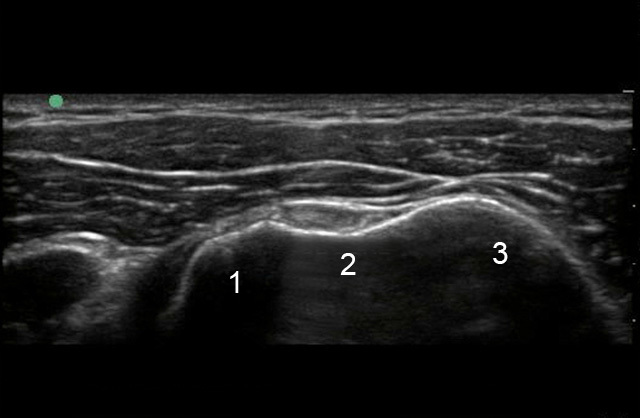

Shoulder Anterior Biceps Groove Image

1. Lesser Tuberosity

2. Bicipital Groove (Biceps Groove)

3. Greater Tuberosity